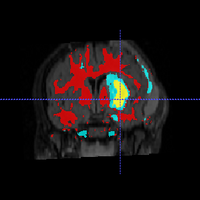

• Segment longitudinal brain MR images with TBI using personalized atlas construction.

• We got two new subjects from UCLA DBP. We processed the data and tested the current algorithm.

• Bo Wang, Marcel Prastawa, Andrei Irimia, Micah C. Chambers, Paul M. Vespa, John D. van Horn, Guido Gerig, A Patient-Specific Segmentation Framework for Longitudinal MR Images of Traumatic Brain Injury, SPIE Medical Imaging 2012.